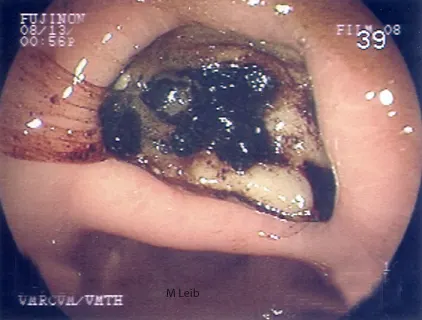

Large gastric ulcer in a 10-year-old Rottweiler. Black clotted blood is adhered to the crater of the large ulcer. The horizontal ridge is the angularis incisura; the antrum is located below the angularis.